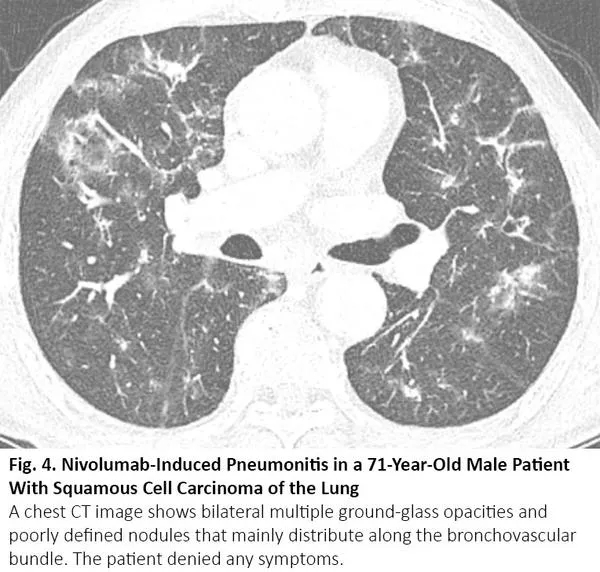

肺癌CT通常表现为结节或肿块,但有时也可表现为空洞。浸润性黏液腺癌是一个著名的例子,可呈现实性病变,伴或不伴磨玻璃样影,类似肺炎。腺癌的特定亚型,包括伏壁式、腺泡型和乳头型为主的腺癌,CT图像可呈现毛玻璃样阴影的区域。16当这些病变发生在肺部多处,其胸部CT可能与COVID-19有相似(图6)。如果既往的胸部CT显示这些病变已经持续存在,则可以与COVID-19区分。

图6. 一位66岁粘液性肺腺癌患者肿瘤复发后的胸部CT